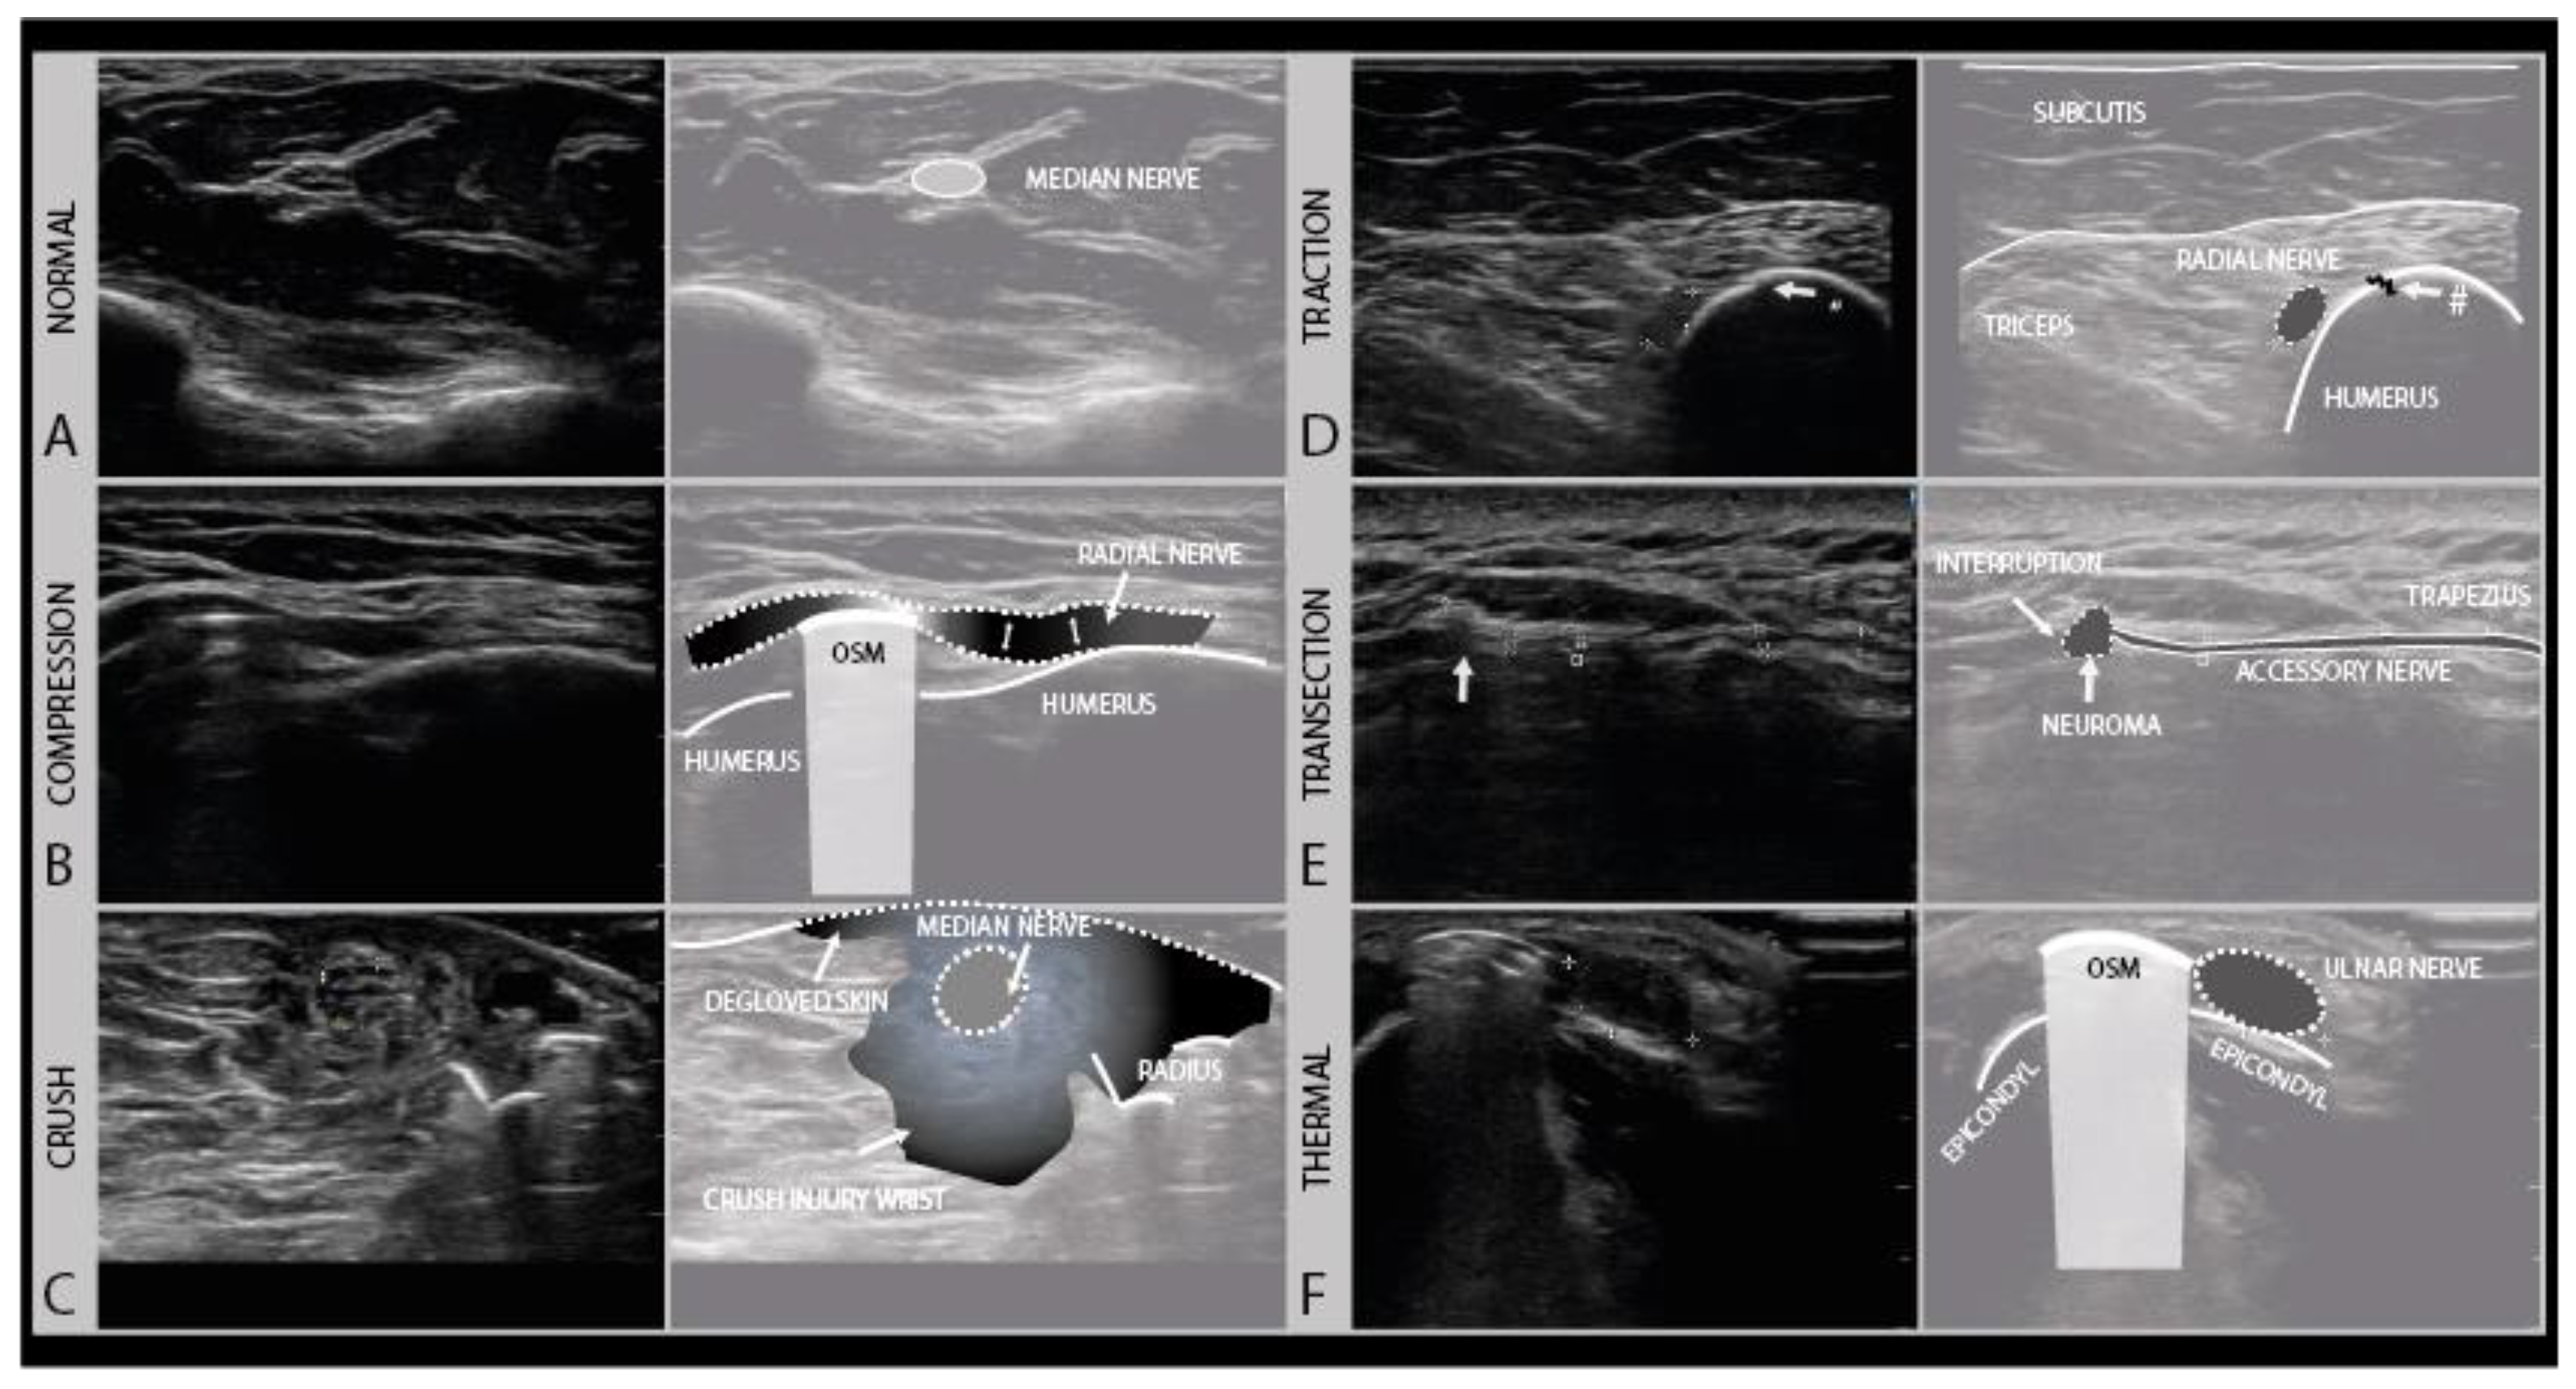

An important aspect for choosing the right therapeutic procedure and thus influencing the prognosis of a nerve injury, is to differentiate between patients with higher Sunderland grade intraneural damage or even the transection of a nerve versus a less severe lesion with preserved nerve continuity and good regenerative potential. To categorize a lesion as major or minor based on imaging (Figure 6), a few typical sonomorphologic signatures can be used, that include the fascicle swelling and hypoechoity of the nerve, the absence of a normal fascicular pattern, and the continuity assessment to detect partial or complete nerve severance with the presence of neuronal stump [28,29].

Figure 6.

Examples of different degrees of axonal damage. Case 1 (A): median nerve swelling following local trauma (fracture), fascicles intact, full recovery without surgery (Sunderland II). Case 2 (B): heterogeneous lesion of the sciatic nerve (peroneal part) of a 19-year-old boy after a scooter accident. Case 3 (C): sciatic nerve damage (Sunderland III) in a 9-year-old girl after a severe car-accident (high-frequency 9–18 MHz). (Intraoperative image kindly provided by PD. Dr. F. Lassner). Case 4 (D): iatrogenic median nerve lesion with loss of nerve continuity (Sunderland V) in a 53-year-old man after arthroscopy of the elbow joint (high frequency 19–24 MHz).

In pure neurapraxia, a Sunderland grade 1 and the least severe lesion, there are either no pathologic findings on ultrasound or just a mild swelling of the nerve with an intact fascicular pattern. A Sunderland grade 2 injury is slightly more severe with axonal damage, and also shows clearly enlarged cross-sectional areas of affected fascicles and nerves at the lesion site because of axonal swelling and edema. Higher grade damage like in patients with Sunderland grade 3 and 4 lesions shows a loss of the normal nerve architecture and echotexture with a disruption of the fascicular pattern and often sizeable hypoechogenic enlargement of the nerve. The more extensive the loss of the normal nerve architecture, the higher the chance that the nerve will develop intraneural fibrosis that hampers or prohibits recovery. For these lesions, a subdivision of the Sunderland system has been described by Millesi [30]. A Sunderland grade 5 lesion shows a transection of the nerve with a loss of nerve continuity. An overview of the nerve injury classification can be found here: https://en.wikipedia.org/wiki/Peripheral_nerve_injury_classification.

Compression injuries can either be acute or chronic. Acute compression injury, such as a peri-operative ulnar compression neuropathy, typically presents with transient paresthesia, numbness and accompanying weakness that recover in weeks. Chronic compression, e.g., carpal tunnel syndrome, is often a progressively worsening condition that persists without proper intervention. Clinically, symptoms start with paresthesia and often also pain, and progress over time to hypesthesia and muscle weakness, depending on the extent of axonal damage [33]. In the case of nerve entrapment, a focal area of nerve enlargement can be seen just proximal to the site of compression. Ultrasound not only helps with localizing the compression site but could also help in identifying its cause. An example of such nerve entrapment, caused by osteosynthesis material in this patient, is shown in Figure 7B. In this case, the radial nerve shows the focal enlargement just proximal to the screw where it is compressed. In addition to a CSA increase, this caliber change can be appreciated quite well in the longitudinal images. When entrapment is severe or chronic, an associated loss of the internal fascicular architecture can be observed as well.

Figure 7.

Examples of different trauma types. The normal transverse aspect of a median nerve in the forearm (A). Local compression injury of the radial nerve by local osteosynthesis material (OSM). Focal enlargement of the nerve diameter proximal to the lesion site can be seen (B). Crush injury of the median nerve at the level of the forearm with surrounding crushed subcutaneous tissue and degloved skin (C). Traction injury of the radial nerve after humeral fracture (#). Swollen and hypoechoic aspect of the radial nerve (D). Iatrogenic transection injury of the accessory nerve after resection of a local lipoma. A stump neuroma can be seen at the site of nerve injury, with a loss of continuity. (E). Swollen and hypoechoic ulnar nerve after thermal injury (hot K-wire) at the level of the medial epicondyle with in situ osteosynthesis material (F).

4.2. Traction Injury

The initial therapy after traction injury is conservative and includes pain management, rehabilitative measures and a minimum follow up after 3 and 5 months. If conservative treatment fails, surgical exploration and reconstruction should be considered within 6 months [37,38]. Depending on the severity of the injury, the nerve will appear hypoechoic and swollen, with or without a disruption of the fascicular architecture. Figure 7D shows an example of a traction injury of the radial nerve, just proximal from a humerus fracture site. In the longitudinal images, the epineurium of the nerve can be seen to be intact.

4.3. Crush Injury

Crush injuries occur from the traumatic compression of the nerve by blunt force, such as from the nerve and surrounding tissue being hit with a bat or ran over by car, getting caught in industrial machinery such as crushing rollers, or pinched between surgical clamps. Crush injuries can cause different degrees of nerve damage ranging all the way from neurapraxia to (partial) neurotmesis. Complete traumatic disruption with nerve transection (i.e., Sunderland grade 5) is rare, but the internal nerve structure can be badly damaged (i.e., Sunderland grade 4). Recovery follows the rules of the Sunderland grading system. Nerve ultrasound at the site of the injury will show a hypoechoic and enlarged nerve with more or less disrupted fascicle architecture and in the acute phase ecchymoses and edema of the surrounding tissues, as shown for example in Figure 7C.

4.4. Thermal Injury

4.5. Transection (“Sharp”) Injury

Complete nerve transection injuries are usually caused by “sharp” accidents, such a knife laceration, glass shard injury, bone drill or gunshot wound. Gunshot wounds, however, are complicated, as they can both damage the nerve directly, or damage the nerve with bone fragments from splintering upon impact, but can also cause severe traction/compression injury from the pressure waves that build up in the bullet trajectory or the subsequent compartment syndrome these pressure changes cause. After complete nerve transection (i.e., Sunderland grade 5, neurotmesis), the distal segment of the nerve will undergo Wallerian degeneration, and there is no chance of recovery across the gap as the proximal and distal nerve ends typically retract. In transection injuries, the nerve ultrasound can be used in the acute setting to reveal the discontinuation of the nerve, often best appreciated in the longitudinal direction. The hallmark is an interruption of the epineurial sheath and the fascicles. In transverse images, the nerve and fascicles in the stumps appear enlarged and hypoechoic, and over time this architecture will become more disrupted as stump neuromas develop (Figure 7E). Surgical treatment, with neurolysis and repair or grafting is the only option for nerve recovery; if this is not possible, tendon transfers and joint stabilization by splinting or arthrodesis should be considered.